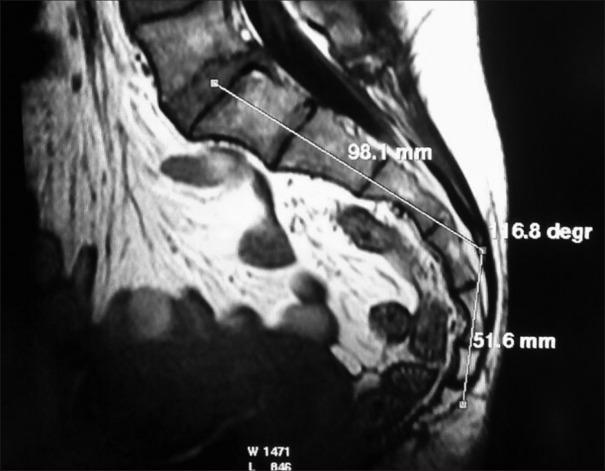

Two groups of patients were identified. Group A was "control group" of 106 normal participants and Group B comprised "study group" of ten patients suffering from idiopathic coccydynia. In all these patients, midsagittal T1-weighted MRI image acquired in supine position was used to calculate SC and IC angles. Data were analyzed, and angles were compared between the study and control groups. Statistical analysis was done with Chi-square test.

In the control group, the average SC and IC angles in the control group were 126.8° and 33.5°, respectively. In the study group, the average SC angle and the average IC angle turned out to be 127.1° and 43.2°, respectively. The difference between the SC angles in the control and study groups was not significant ( = 0.7), whereas the difference between the IC angles in the two groups was significant ( = 0.002).

From our study, we observed that the IC angle shows a decreasing trend with increasing age. In addition, increased IC angle was identified as a possible cause of idiopathic coccydynia.